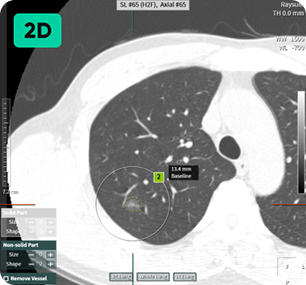

자동 결절 감지

및 폐 RADS 계산

영상 인공지능을 활용해 저선량 흉부 CT에서 놓치기 쉬운 폐 결절을 탐지하고 분석합니다.

미세 결절을 발견하면 기본 정보, 결절 개수, 크기 및 상태, RADS 범주 등 다양한 정보를 얻을 수 있습니다. 폐암으로 발전할 가능성이 있는 소견도 미리 확인하여 작업 시간을 단축하고 사례에 따라 효율적인 판독을 가능하게 합니다. 미세 결절 검출: 결절 개수, 크기, 상태, RADS 범주에 대한 포괄적인 정보 제공 잠재적 폐암 발생을 조기에 발견하여 시간 효율적인 스캔 판독을 가능하게 합니다.

작은 것부터 큰 것까지 다양한 크기의 결절 감지